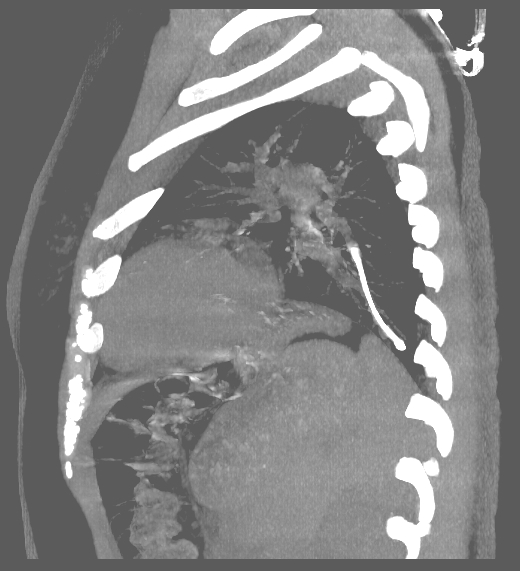

A twenty nine years old lady diagnosed as Carcinoma left breast underwent breast conservation surgery (pT2N2aM0, ER positive PR positive Her 2 neu positive) and presented for adjuvant chemotherapy. She was planned for adjuvant chemotherapy, radiotherapy and hormonal therapy as per standard guidelines. Chemoport reservoir was placed in the chest wall – right infraclavicular fossa and chemoport catheter was placed in the right subclavian vein. Post-procedure chest x ray revealed proper placement of the chemoport. She underwent first cycle of adjuvant chemotherapy with Docetaxel, Carboplatin and Trastuzumab without any complications. When she presented for second cycle (45 days after chemoport insertion), she was asymptomatic. However, there was no backflow of blood from the chemoport reservoir. Chest X ray revealed fragmentation and embolization of chemoport catheter. ECG showed normal sinus rhythm. Non Contrast CT scan chest was done, which revealed that the distal fragment of chemoport catheter had embolized to left pulmonary artery lower lobar branch, having migrated across the right atrium, right ventricle, main pulmonary artery and its left branch (Figure 1). After informed consent, retrieval of distal fragment of chemoport catheter was done in cath lab under local anesthesia under fluoroscopic guidance by Interventional Radiology team. It was retrieved from left pulmonary artery lower lobar branch in a procedure lasting forty minutes. The right femoral vein was punctured, 10 Fr Cordis sheath was introduced into the femoral vein, left pulmonary artery was cannulated using cobra 5 Fr catheter and then it was exchanged with snare over the guide wire. The left posterior inferior branch of pulmonary artery was selectively cannulated using Terumo guide wire and Cobra catheter. The tip of the foreign body was snared using Sequre snare system (4Fr, 10mm) and pulled through the pulmonary artery (Figure 2). The length of the catheter fragment was 4cm (Figure 3-9). The next day, chemoport reservoir and the proximal fragment of chemoport catheter was retrieved by surgery under local anesthesia. Patient tolerated both procedures well and was discharged on the third day.

Figure 2 MIP image sagittal view NCCT Chest showing distal fragment of chemoport catheter in the left pulmonary artery lower lobar branch.